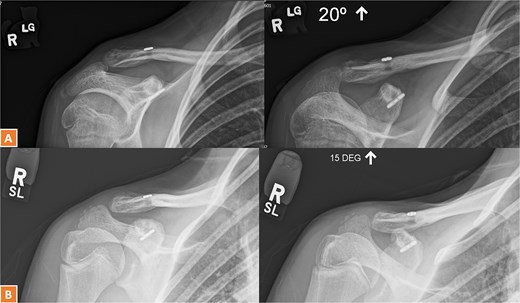

(A, B) Radiographs showing complete healing of the first case and union at 3 months and 12 months post-operatively.

A 15-year-old male sustained a displaced Neer type IV lateral clavicle fracture during a rugby match, presenting with acute pain, deformity, and dorsal displacement without neurovascular compromise (Fig. 1). Imaging confirmed the diagnosis, and open reduction with TightRope and Fiber-wire reinforcement was performed. Early rehabilitation was initiated following short-term immobilization. At 6 weeks, the patient achieved pain-free shoulder function and radiographic stability. By four months, he regained full range of motion and returned to non-contact sports. Minor peri-scar numbness persisted, but imaging confirmed fracture union, and he was cleared for contact activities (Fig. 2A–B).